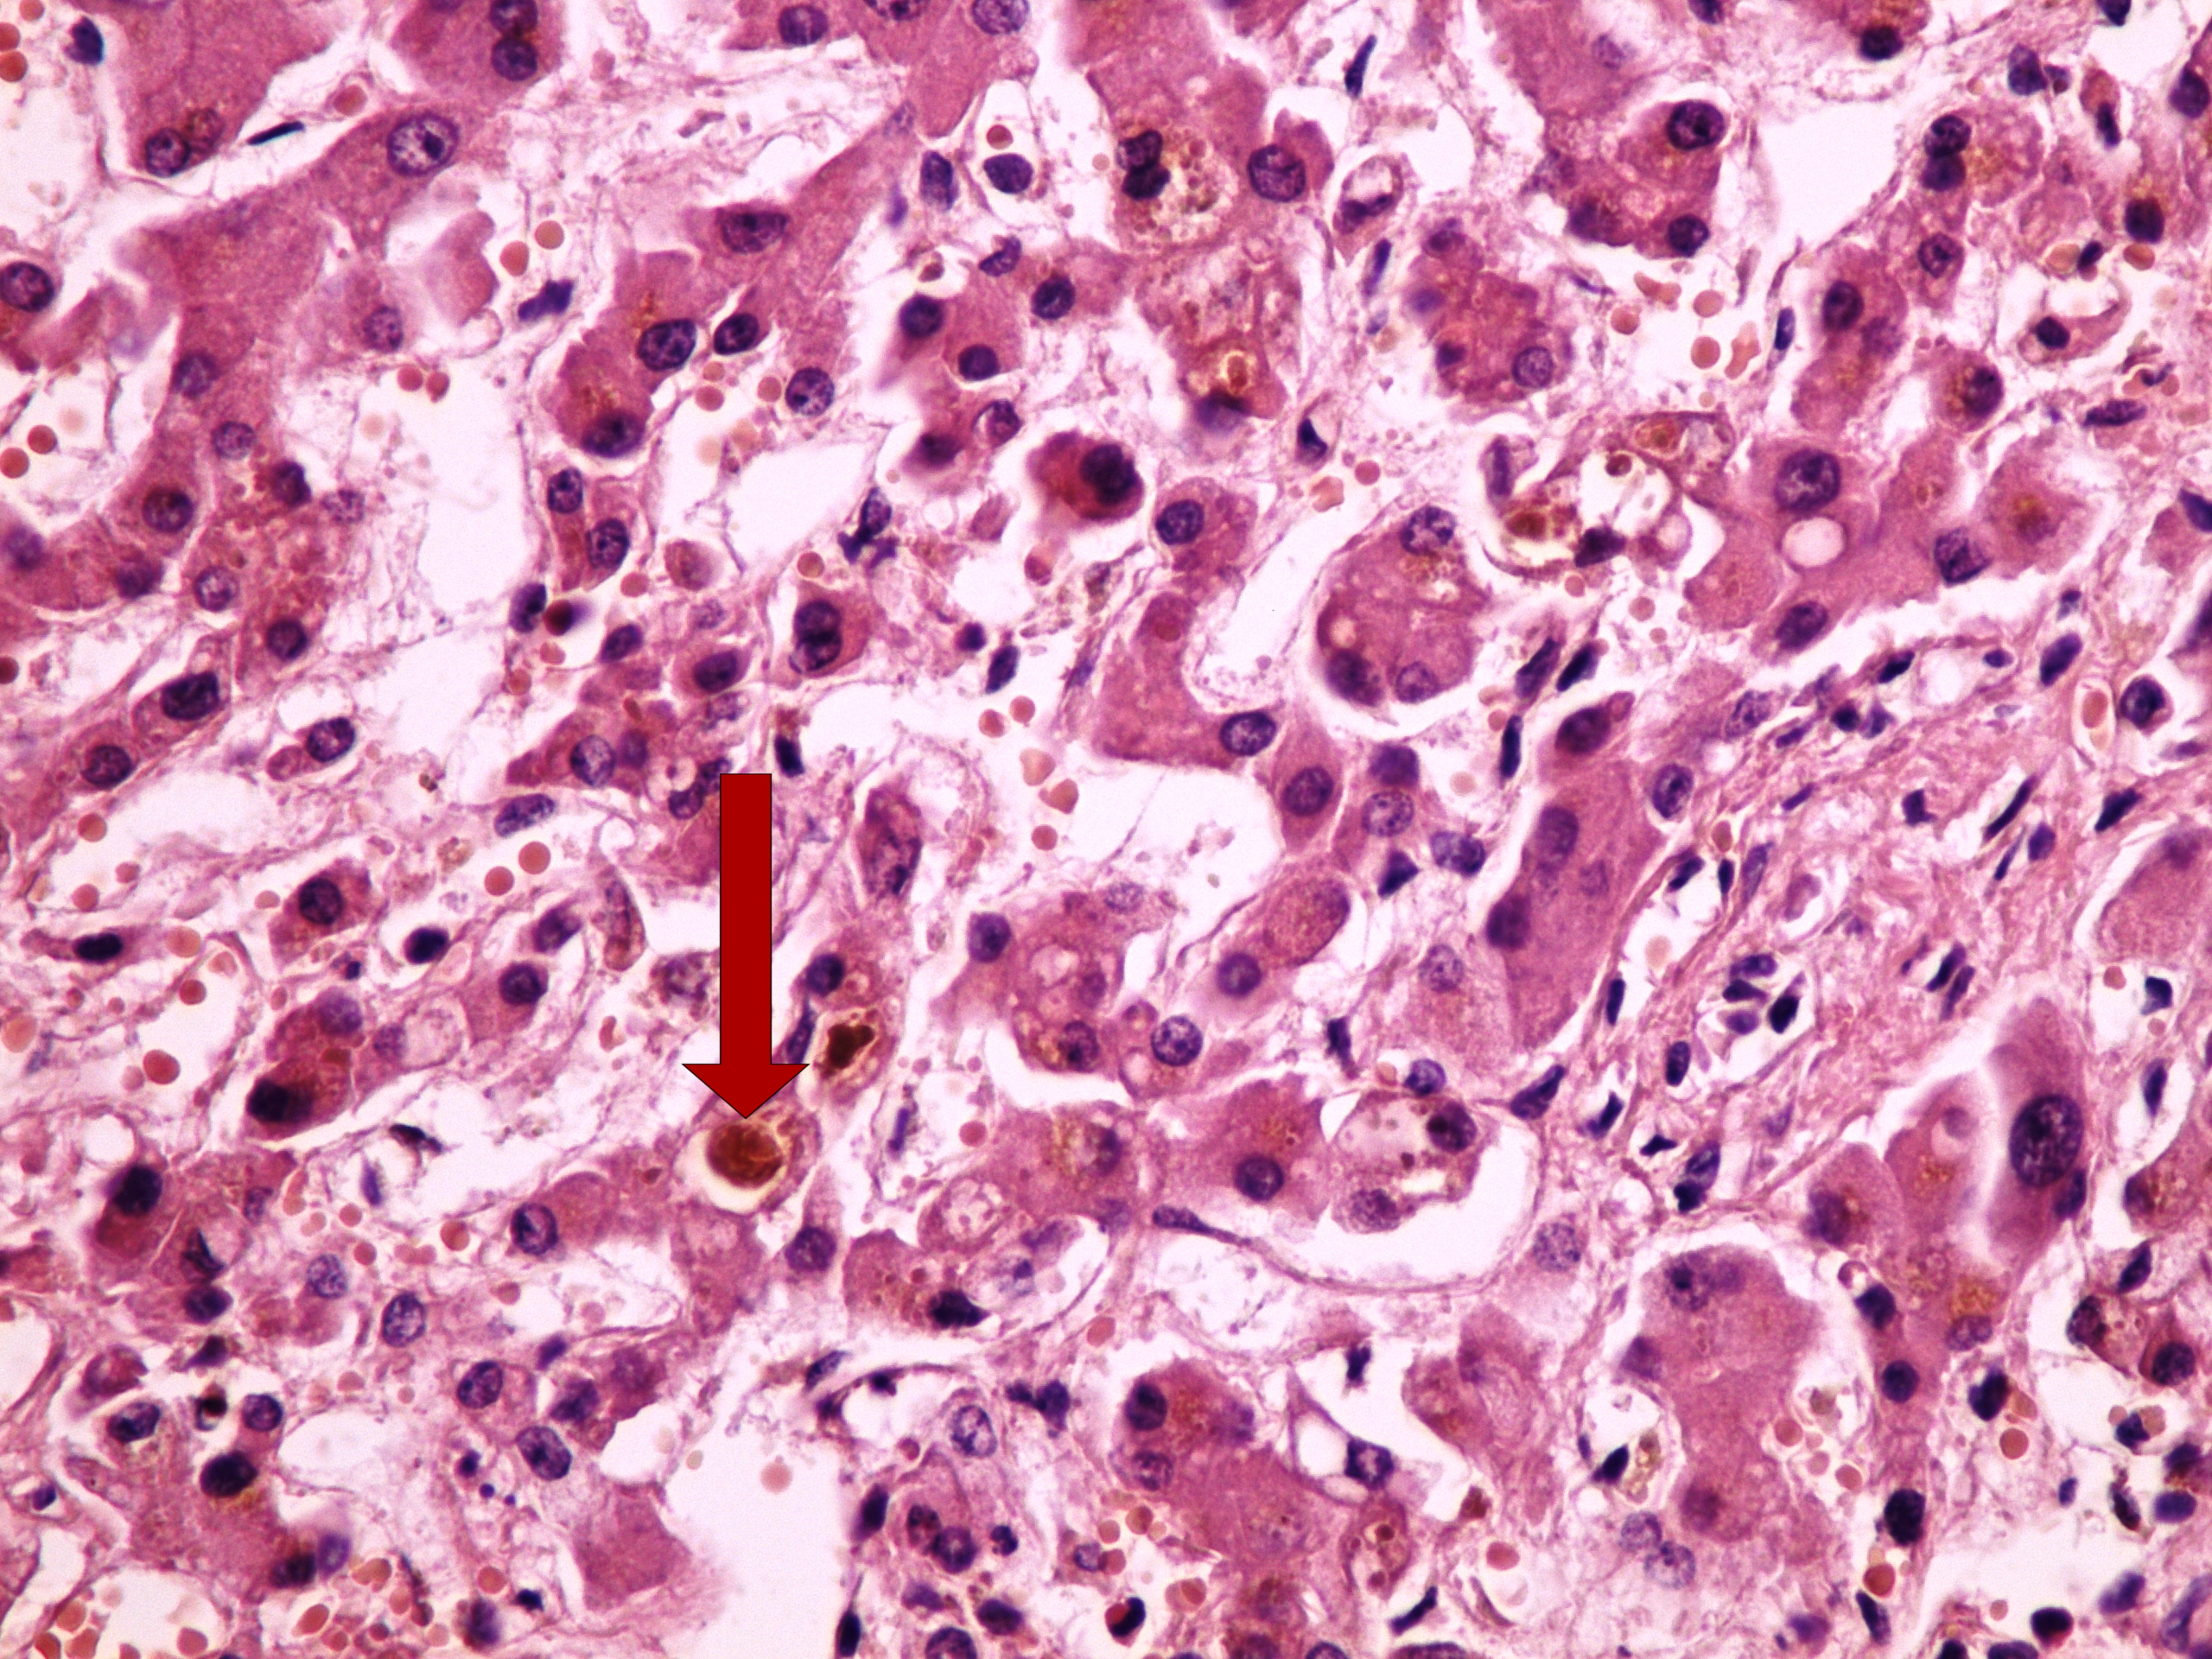

Preparát č.5 a č.6 - bilirubin

Struktury

- žlučový "trombus" v játrech